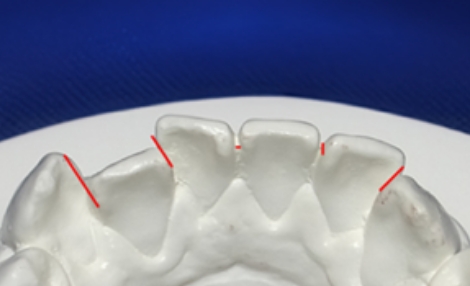

観察方法はPARスコアではなく、もう少しダイレクトな評価になるリトル教授らの方法を使いました。つまり右図のように、後戻りが一番現れやすいと言われている下の前歯において、歯と歯の接触点間の距離をmm単位でデジタル写真上で計測し、それらの合計のミリ数を「指数」とするものです。歯並びが綺麗であれば“0”に近い数字になり、数字が大きいと悪い歯並びを意味します。この写真の歯と歯の接触点間の距離の合計は9.3mmでしたから、指数は9.3になります。